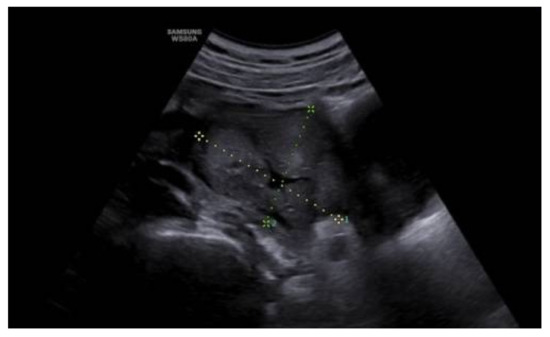

Aggressive Pelvic Angiomyxoma in a Patient with Twin Pregnancy: Diagnosis, Treatment, and Clinical Complications in Light of the Literature

by Carmen Imma Aquino, Raffaele Tinelli, Alessandro Libretti, Riccardo Bertinato, Renzo Luciano Boldorini, Michele Giana, Felice Sorrentino, Luigi Nappi, Valentino Remorgida and Daniela Surico

Medicina 2023, 59(8), 1417; https://doi.org/10.3390/medicina59081417 - 3 Aug 2023

(1) Background: Aggressive angiomyxoma is a mesenchymal cancer that is rare during pregnancy. It is a neoplasm that relapses and infiltrates the nearest structures. Our aim is to evaluate the management and outcomes of an observed case, in light of the current literature. (2) Methods: We observed this condition at the “Maggiore della Carità” Hospital in Novara (Italy) in a patient with an initial twin pregnancy and a suspected pelvic mass. The words “angiomyxoma” and “pregnancy” were searched on the main online scientific search sources (PubMed, Google Scholar, Scopus, WES, and Embase, etc.). (3) Results: The patient underwent surgery with a complicated follow-up, but recent negative controls. We analyzed the literature about the topic and found only 24 similar clinical cases. (4) Conclusions: Considering the current literature, it is useful to assess an aggressive angiomyxoma in the differential diagnosis of soft masses in pregnant women. The treatment of choice is surgical excision, and vaginal delivery is feasible. The therapeutic decision depends on each case. Full article

Figure 1